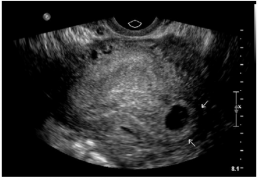

Ovarian Torsion

- Bimodal age distribution: young women (15-30yo) and post-menopausal women

- Typically occur in enlarged ovaries (>5cm)

- Sonographic signs associated with torsion

- Enlarged ovary from edema, engorgement, hemorrhage

- Midline ovary

- Free pelvic fluid

- Underlying ovarian lesions

- Peripherally displaced follicular cysts

Hemorrhagic ovarian cyst with blood clot Large midline ovary with multiple peripherally located follicular cysts (torsion)

Large midline ovary with multiple peripherally located follicular cysts (torsion) Absent color doppler and venous and arterial waveforms (torsion)